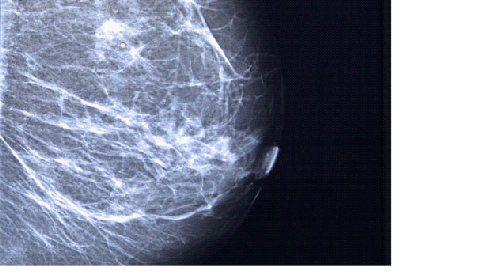

Mamografi

Meme kanseri ne kadar erken teşhis edilirse tedavisi o kadar kolay olur.

Memenin ilaçla çekilen röntgen filmi olan mamografi meme tümörlerini hissedebilecek kadar büyümeden saptayabilir.

Dünya Sağlık Örgütü verilerine göre ve ülkemizde ortalama risk seviyesinde olan, 45 yaşını geçen kadınların yıllık mamografi çektirmeleri önerilmektedir.

50 yaşına kadar tüm kadınların en az bir kez doktora meme muayenesi yaptırmaları gerekmektedir.

50 yaşından 75 yaşına kadar risk gurubundaki tüm kadınlarda 2 yılda bir mamografi taraması yapılmalıdır.

75 yaşından sonra ise mutlaka doktora danışılarak davranmak ve takip edilmek gerekir.